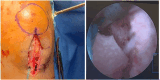

Graft-tunnel mismatch (GTM) is a known technical challenge that can occur with anterior cruciate ligament reconstruction when using a patellar tendon autograft. Two-incision anterior cruciate ligament reconstruction is a well-established technique with excellent outcomes and can serve as an excellent tool to prevent GTM. Traditionally, 2-incision femoral tunnel drilling has been performed using an over-the-top guide through a lateral incision, but more modern retrograde reamer guides can allow this to be done percutaneously. We detail how a minimally invasive 2-incision femoral tunnel drilling technique can be used in patients with patellar tendon lengths that are longer than average to avoid GTM.